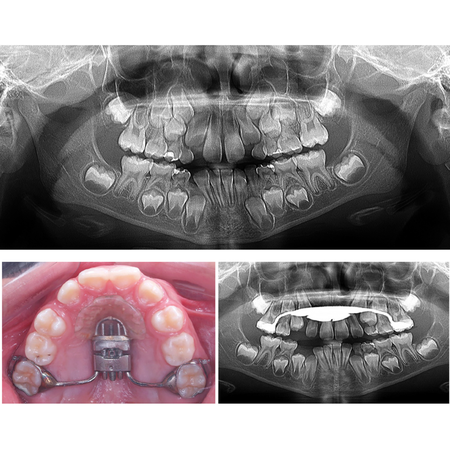

Disjunção palatina anteroposterior e a pré-maxila

OBJETIVO: Fundamentar biologicamente a proposta de disjunção palatina anteroposterior em casos devidamente selecionados. METODOLOGIA: Utilizou-se a amostra de dissertação de mestrado de Trevizan (2018) e suas inferências, para funda...

Disjunção Palatina Disjunção palatina anteroposterior

Anteroposterior palatal disjunction and the premaxilla

OBJECTIVE: To biologically substantiate the proposal of anteroposterior palatal disjunction in properly selected cases. METHODOLOGY: The sample from Trevizan’s (2018) master’s dissertation and its inferences were used to support the...

Palatal disjunction Anteroposterior palatal disjunction

Disyunción palatina anteroposterior y la premaxila

OBJETIVO: Fundamentar biológicamente la disyunción palatina anteroposterior propuesta en casos debidamente seleccionados. METODOLOGÍA: La muestra de la tesis de maestría de Trevizan (2018) y sus inferencias se utilizaron para fundame...

Disyunción palatina Disyunción palatina anteroposterior